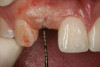

Figure 4  Characterization of the interproximal bone and tooth contacts: A periapical radiograph assists in measuring the distance from bone crest to the adjacent tooth contact points for missing tooth No. 8. The mesial bone crest to the adjacent tooth contact distance is < 5 mm, while the distal bone crest to adjacent tooth contact distance is > 6 mm (Fig 4). One-year following implant placement, conservation of these dimensions is revealed (Fig 5). The clinical photograph (Fig 6) of the lateral incisor adjacent to tooth No. 8 implant crown demonstrates that the absence of distal interproximal (papilla) fill related to the observed bone crest to contact distance exceeds 6 mm.

Figure 4

Figure 5  Characterization of the interproximal bone and tooth contacts: A periapical radiograph assists in measuring the distance from bone crest to the adjacent tooth contact points for missing tooth No. 8. The mesial bone crest to the adjacent tooth contact distance is < 5 mm, while the distal bone crest to adjacent tooth contact distance is > 6 mm (Fig 4). One-year following implant placement, conservation of these dimensions is revealed (Fig 5). The clinical photograph (Fig 6) of the lateral incisor adjacent to tooth No. 8 implant crown demonstrates that the absence of distal interproximal (papilla) fill related to the observed bone crest to contact distance exceeds 6 mm.

Figure 5